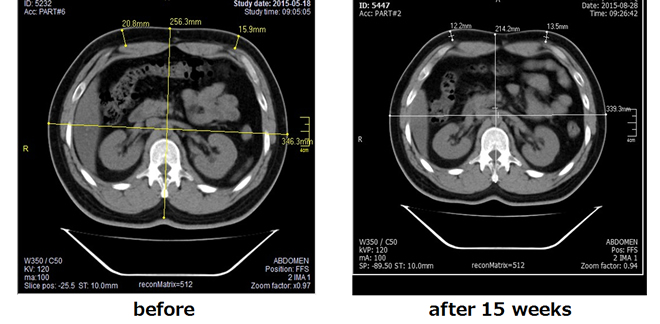

LIPOcelは、コンタクトクーリングシステムを使用することで90℃の熱を脂肪細胞に加えることができる結果、施術後1~2週間程度でネクロ―シスによる即時効果が現れ、その後8~12週間ほどかけてゆっくりとアポトーシスの効果現れてきます。